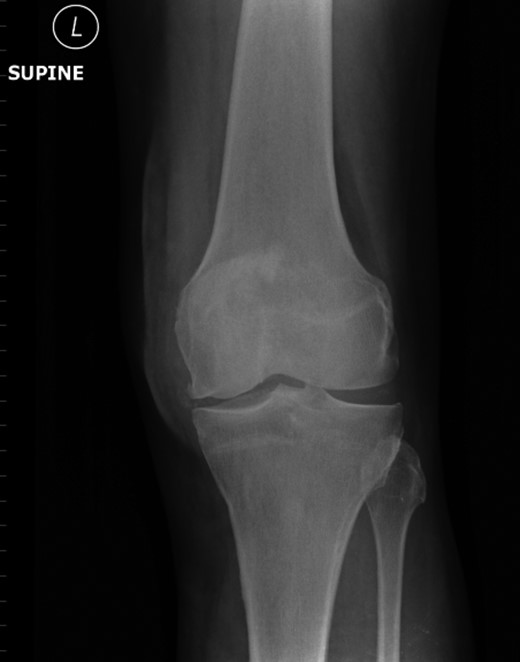

Nineteen months earlier the patient had consulted his general practitioner complaining of left knee pain. Radiographs performed at that time were reported to show joint space narrowing within the patello-femoral compartment as well as early joint space narrowing within the medial compartment. A subchondral lucency was also noted within the patella which was described as a subarticular cyst secondary to the previously mentioned patello-femoral degeneration (Figs 1–3).

The absence of associated features of systemic disease, as well as radiographic appearances in keeping with early patello-femoral osteoarthritis (OA), account for the delay in diagnosis. The initial images suggest mild degeneration but, whilst subarticular cysts are a radiographic feature of OA, the lesion shown in this case is larger than would be expected with the level of disease shown elsewhere in the joint.